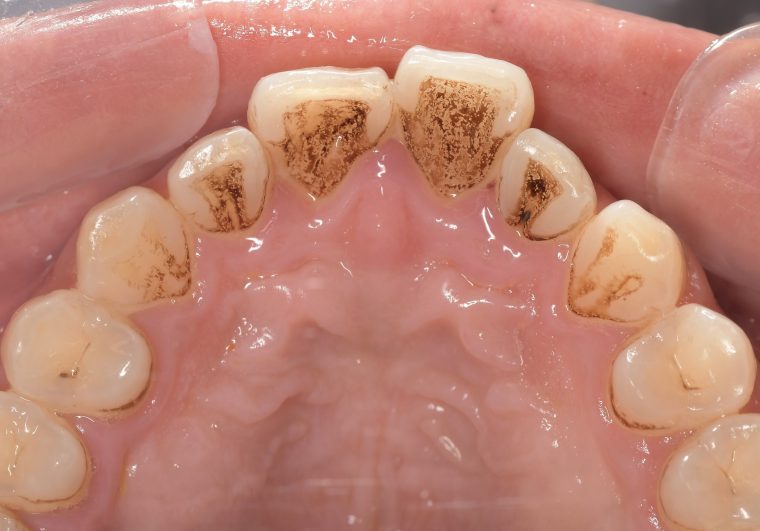

CASE 4

Before

After

基本情報

| 年齢・性別 | 52歳・女性 |

|---|---|

| 主訴 | クリーニングしたい |

| 治療内容 | スケーリング・PMTC |

| 治療期間 | 60分 |

| 治療費 | 約7,000円 |

| リスク・副作用 | 知覚過敏、歯肉退縮 |

| 治療方針 | 歯石とステインを除去して、今後は定期検診でのクリーニングと併せてガムピーリングやホワイトニングを行います。 |

| 担当者所見 | 歯肉の色素沈着が目立つため、ガムピーリングを行いながらホワイトニングを行うことをおすすめします。 |